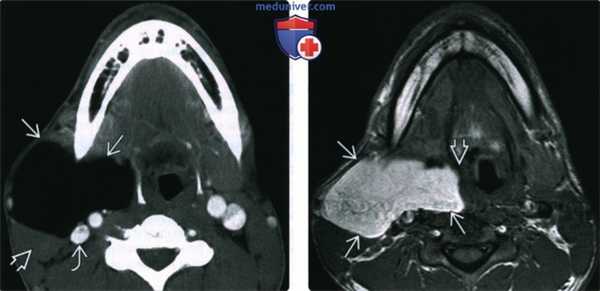

(Слева) КТ с КУ, низкоплотное однородное образование правой половины шеи с четкими контурами. Пациент был направлен с «новообразованием околоушной железы». Образование смещает грудино-ключично-сосцевидную мышцу, сонную артерию и яремную вену кзади. Признаков местной инвазии не определяется.

(Справа) МРТ Т1ВИ без гадолиния. Сигнал от образования однородный и гиперинтенсивный. Опухоль прилежит к стенке глотки в и смещает ее влево. На Т2ВИ FS и на контрастных Т1ВИ сигнал от образования полностью исчез.